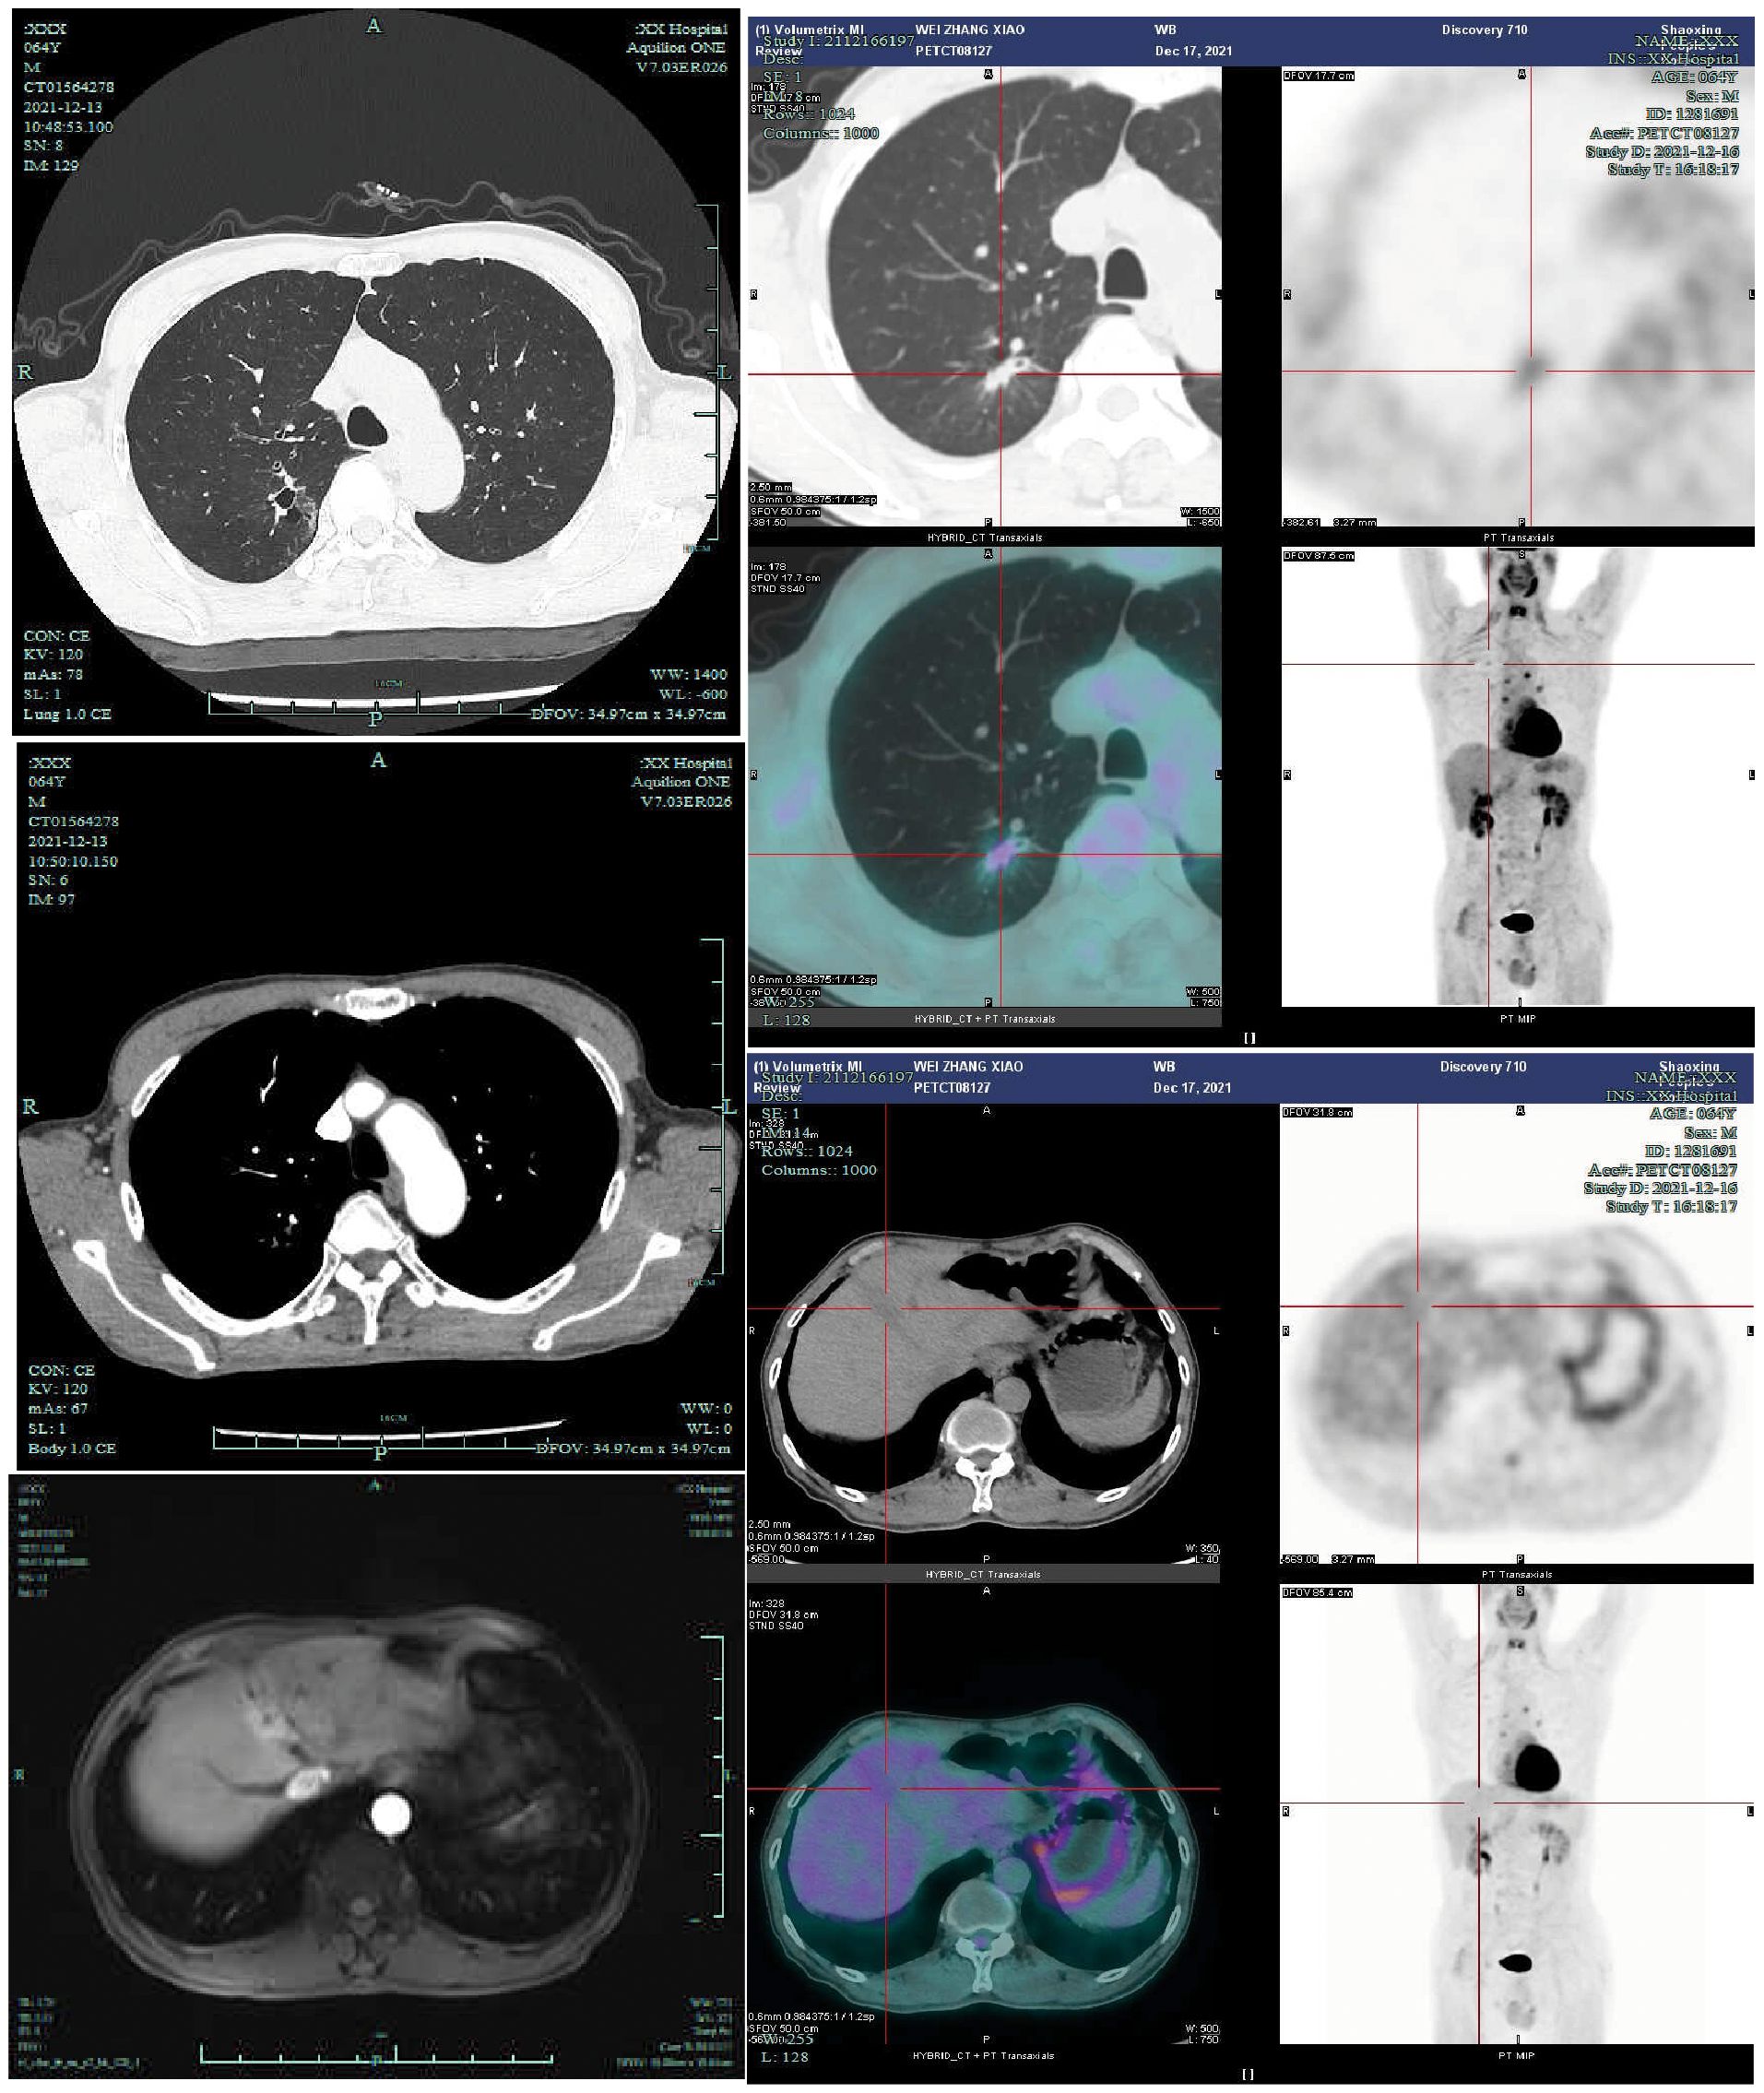

The patient demonstrated satisfactory systemic treatment response with complete metabolic resolution of both pulmonary and hepatic lesions on preoperative PET-CT (Figure 2). Following thorough MDT evaluation and considering the patient’s strong surgical preference, right upper lobectomy with mediastinal lymph node dissection was performed via video-assisted thoracic surgery on December 21, 2021. Histopathological examination revealed lymphocyte infiltration without residual tumor cells in both the resected specimen and dissected lymph nodes, confirming pCR (Figure 3). Postoperative immunotherapy maintenance was irregular due to COVID-19 pandemic constraints, with only two subsequent administrations of tislelizumab on March 25 and May 14, 2022. During the most recent outpatient follow-up on January 16, 2025 (Supplementary Figure 2) and subsequent telephone contact, the patient remained disease-free with excellent performance status, demonstrating durable treatment response without evidence of recurrence or metastasis.

Figure 2

Figure 2. Preoperatively, the patient underwent contrast-enhanced chest CT (2021-12-13), contrast-enhanced liver MRI (2021-11-9), and PET-CT examinations (2021-12-17). Preoperative PET-CT demonstrated a right upper lung nodule with a maximum standardized uptake value (SUVmax) of 1.85, while the liver mass exhibited physiological FDG uptake.